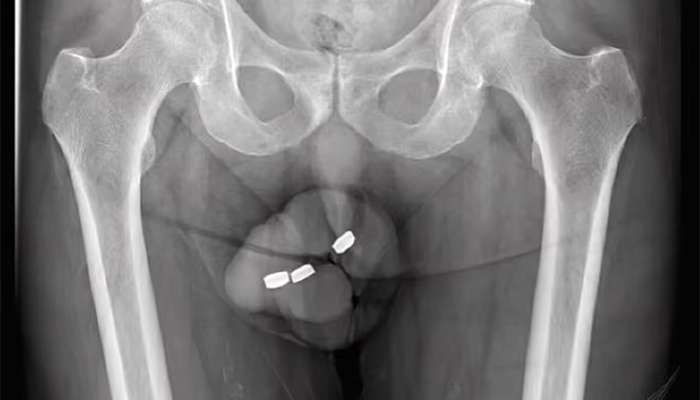

Həkimlər